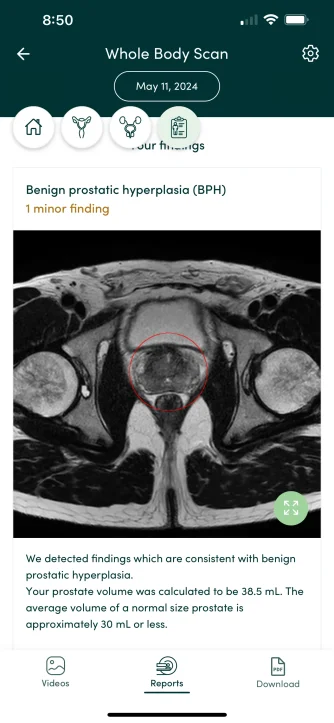

I did a screening prenuvo scan ( whole body mri) and one finding was enlarged prostate, normal is less than 30 ml and mine was 38.5ml

I cannot find this info anywhere but I’m hoping it just because I’m big, 6’5 240 pounds (not fat, pretty lean). I am on trt and my TT currently are 1500 ng/dl… I know I’ll decrease dose to make my TT 700 now, but any thoughts? I’m too young for this!